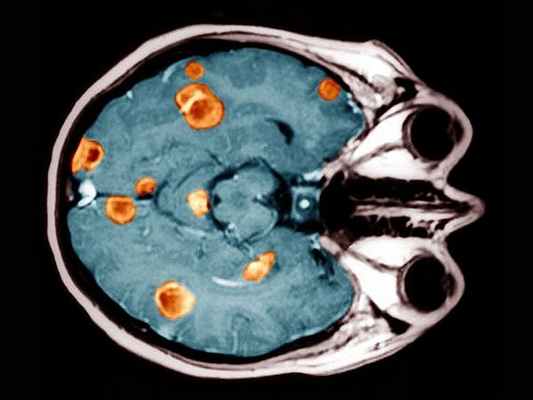

Клинический пример № 1:

Пациентка К., 56 лет, обратилась амбулаторно в кабинет магнитно-резонансной томографии по поводу головокружений, шаткости походки.

В анамнезе рак правой молочной железы, резекция молочной железы, прохождение курсов химиотерапии.

При исследовании головного мозга путем магнитно-резонансной томографии в различных режимах выявлен единичный метастатический очаг поражения головного мозга, локализованный в левом полушарии мозжечка, с наличием перифокального отека, распространяющегося на большую часть мозжечка. Данная локализация метастаза определяла симптоматику (головокружение, шаткость походки).

При проведении внутривенного контрастного усиления определены более точные размеры и границы метастатической опухоли.